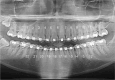

Materials and methods: Forty-five patients were randomly assigned to three bonding groups (G1 [n = 15], G2 [n = 15], and G3 [n = 15]). Evaluation after the alignment and leveling phases used two parameters of the objective grading system of the American Board of Orthodontics for root parallelism and posterior marginal ridges, assessed using panoramic radiographies (PR I and PR II), a digital model, and a plaster model. Blinding was only applied for outcome assessment. No serious harm was observed except for gingivitis associated with plaque accumulation.

Results: Although G3 showed better numerical results, they were not statistically significant in the radiographic or model evaluations (P > .001). Mean chair time was significantly shorter in G3 (1.1 ± 11.8 min) vs. G1 (56.7 ± 7.3 min) and G2 (52.8 ± 8.3 min; P < .001).